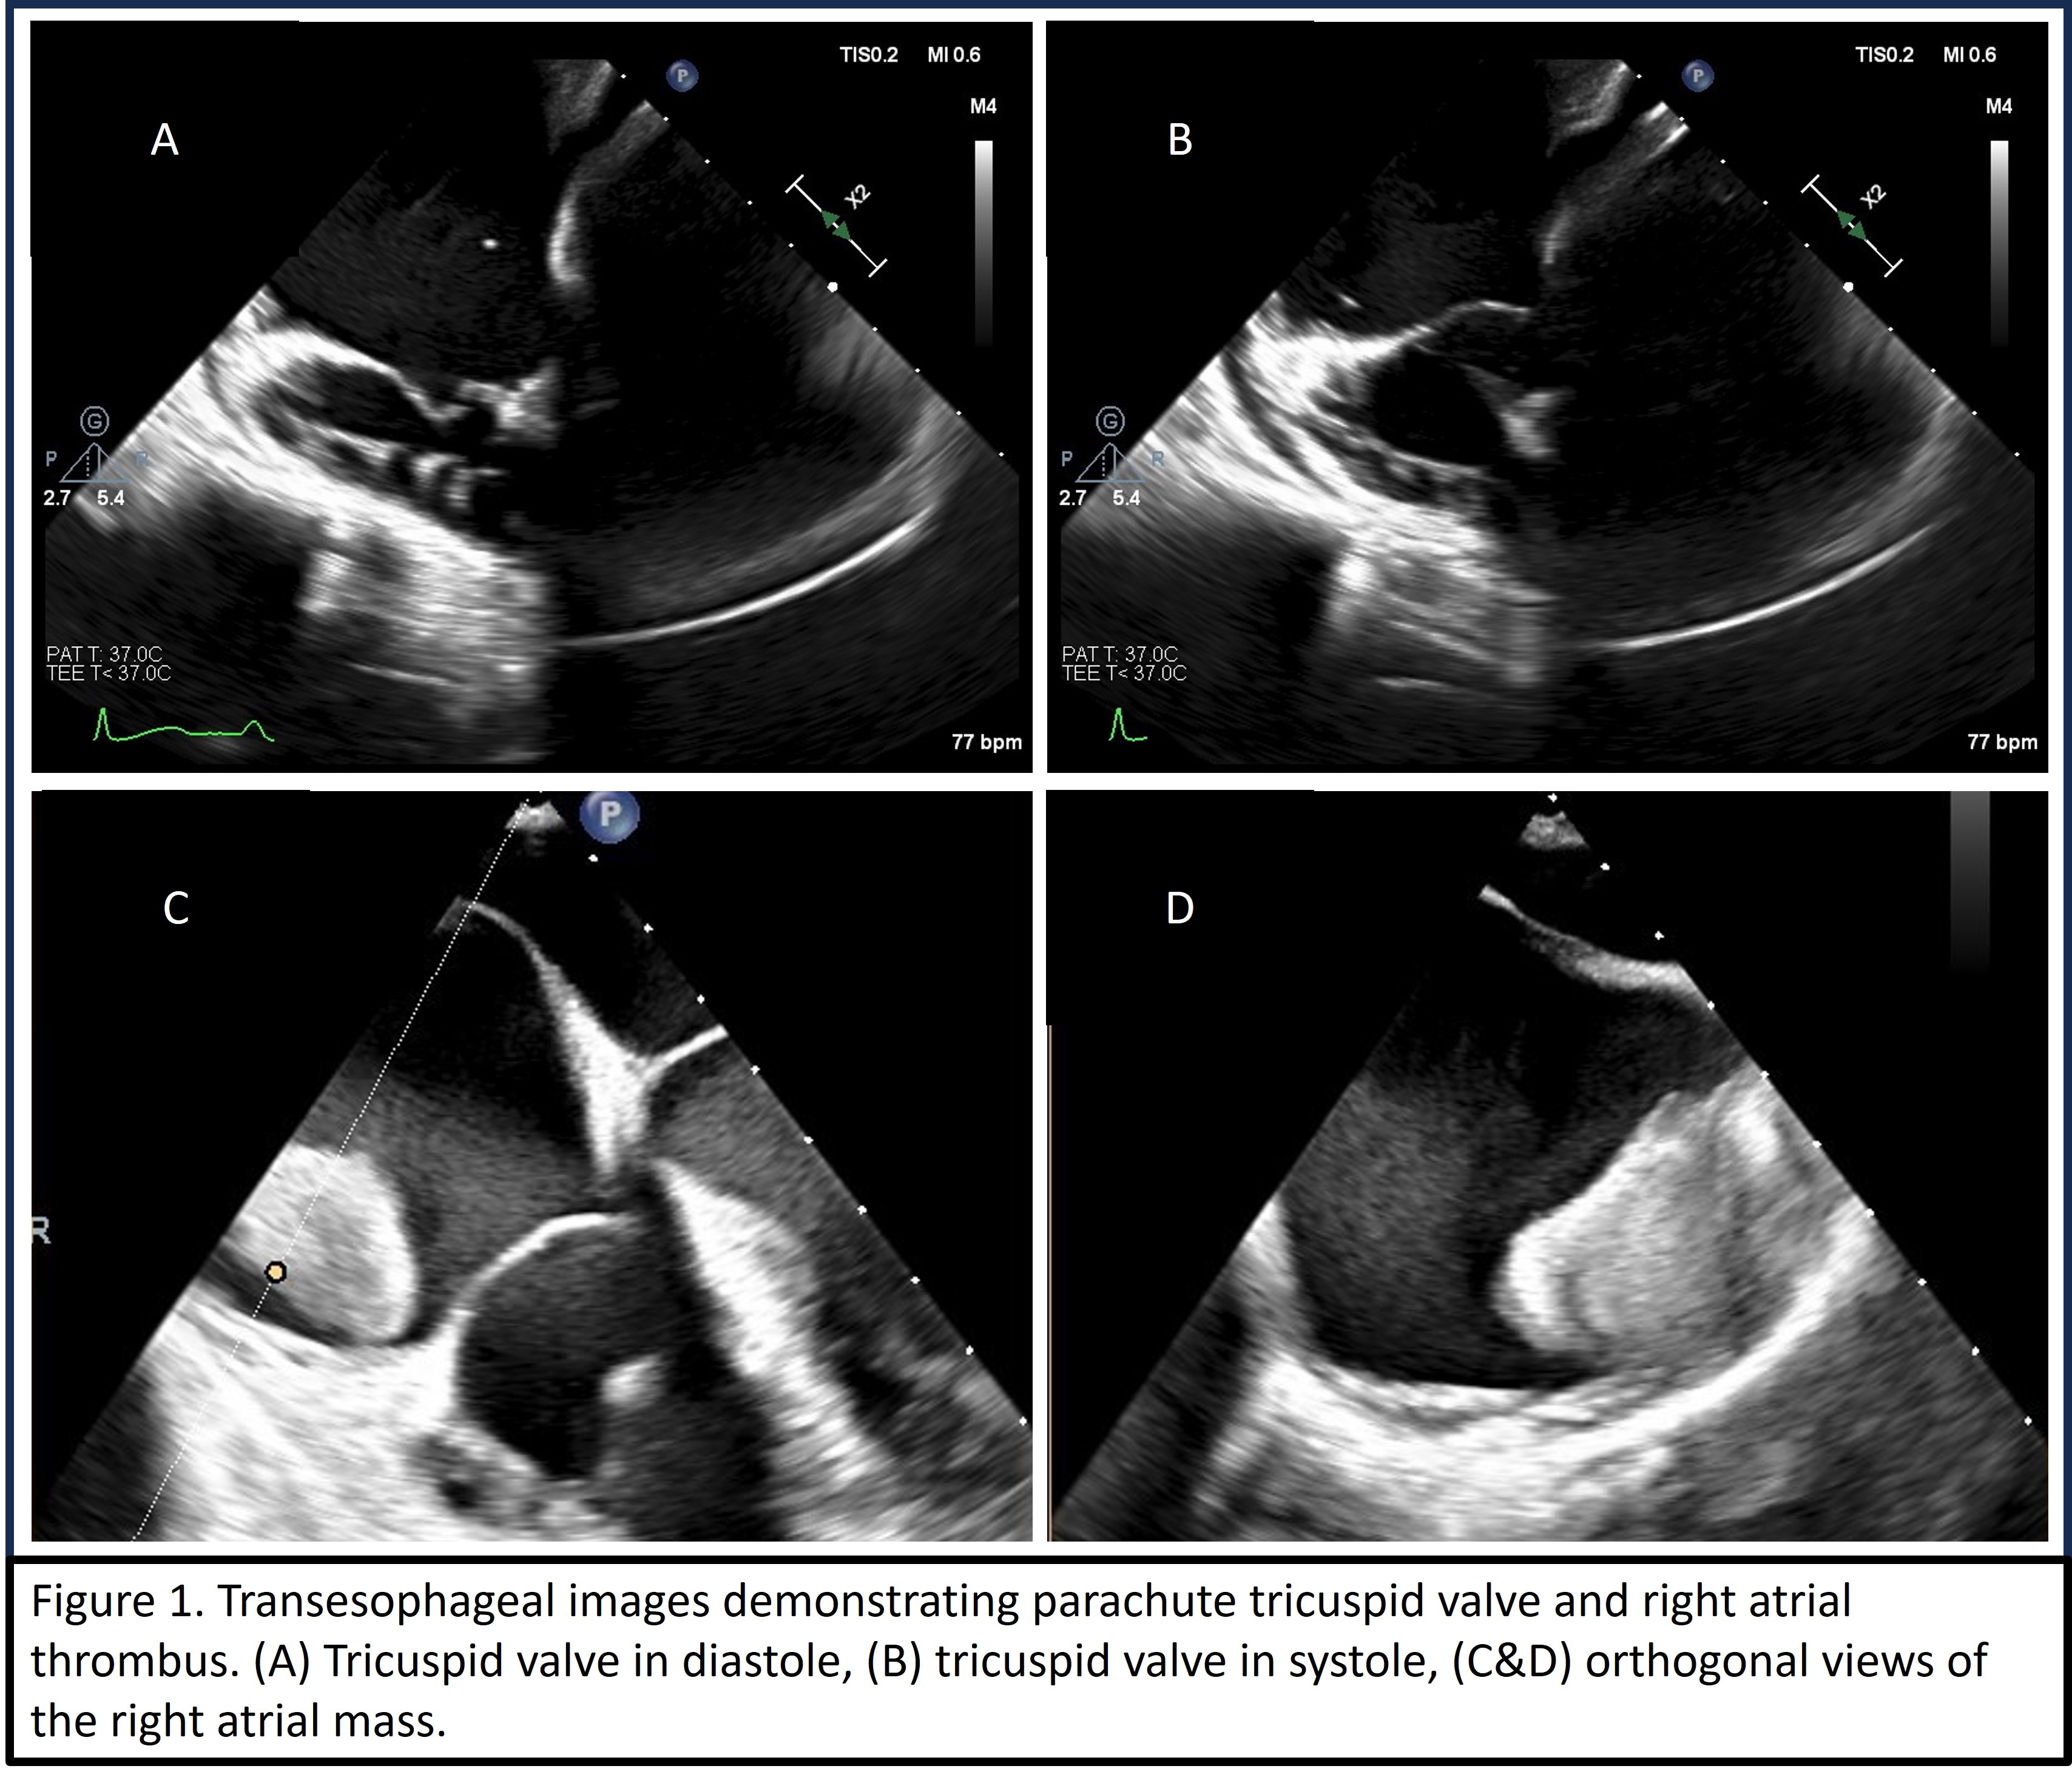

The patient underwent a transesophageal echocardiogram that demonstrated a layered RA thrombus with mobile components, patent foramen ovale, and a congenitally dysplastic ‘parachute’ tricuspid valve (TV) with apical displacement of septal leaflet (Figure 1). It was noted that TV chordae tendinae attached to a single papillary muscle which was contiguous with the moderator band. Cardiac MRI confirmed these findings and that the RA mass was a thrombus. Despite anticoagulation and antibiotics, the patient continued to have intermittent fevers. PET CT demonstrated hypermetabolism of the RA thrombus and therefore suction thrombectomy was performed. Pathology revealed thrombus with purulent debris; however, no organisms were identified. With antibiotics and anticoagulation, the patient improved clinically and was discharged with plans for outpatient follow up.